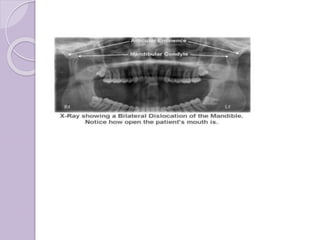

Subluxation and dislocation

Precipitating factors :

๏‚— Trauma

๏‚— Forceful wide opening โ€ฆ

Clinical features :

a) Subluxation

Normal mouth opening but with a click

Painless

Deviation

b) Dislocation

โ€ขInability to close mouth โ€œOPEN LOCKโ€

โ€ขDifficulty in speech

โ€ขDrooling saliva

โ€ขLip incompetency

โ€ขIn acute, pain in preauricular region

โ€ขUsually bilateral

โ€ขWhen palpated over preauricular region,-

emptiness in joint space

โ€ขPatient looks anxious